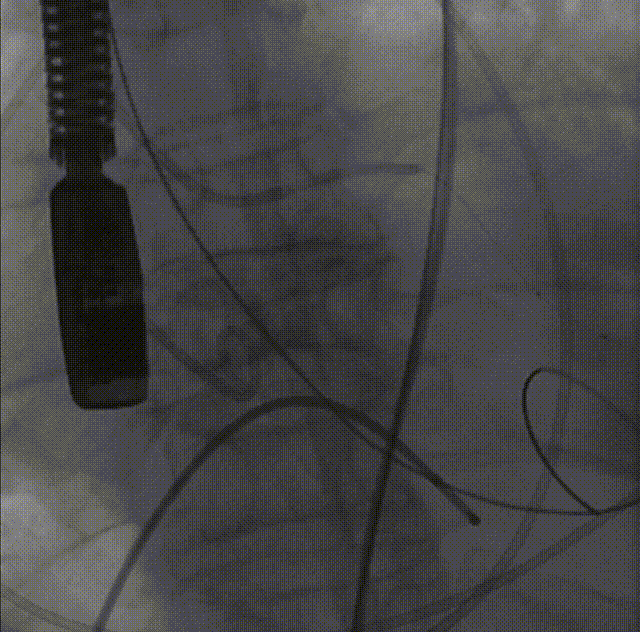

26VenusAplus+snare

瓣膜内22mm球囊后扩张,左冠无显影

LM烟囱支架植入4.0*30mm